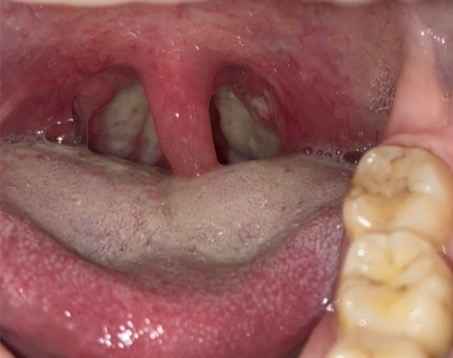

急性扁桃炎

扁桃腺は、口と咽頭の間にある構造です。ウイルスや細菌の感染症にかかると、それを扁桃炎と呼びます。

この症状は、喉に膿の点があり、その部分が腫れているため、食べ物を飲み込むことと正常な痰の流れの両方を妨げ、副鼻腔炎を引き起こす可能性がある最も一般的な症状です。

発熱、喉の痛み、口臭、食欲不振も一般的な症状です。